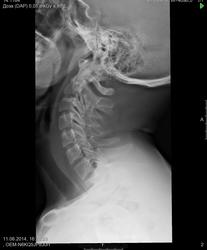

Пол пациента: Мужской пол Тип патологии: Метаболическое заболевание Область исследования: Скелетно-мышечная система Методы исследования: Rg Есть ли здесь функциональный блок сегментов C5-C6, C6-C7? https://radiomed.ru/sites/default/files/styles/case_slider_image/public/user/19785/m_c_spine_20140611_155947.jpg?itok=ohD7GSmA ID:38807 Ср, 11/06/2014 - 18:22 #1 Андрей Юрьевич Не на сайте Был на сайте: 2 недели 12 часов назад Зарегистрирован: 16.11.2008 - 22:16 Публикации: 18098 Блока нет. Блок - это когда нет движений, а тут они есть. Андрей Юрьевич Чт, 12/06/2014 - 11:13 #2 И.Бондаренко Не на сайте Был на сайте: 2 дня 6 часов назад Зарегистрирован: 13.09.2011 - 22:55 Публикации: 9206 Признаков нестабильности нет.

Блока нет. Блок - это когда нет движений, а тут они есть.

Признаков нестабильности нет.